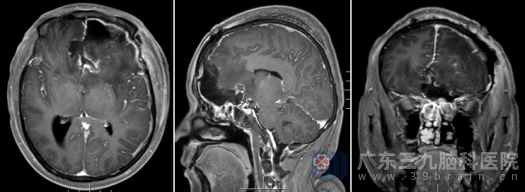

术后MR

术后复查头颅MR显示:原病灶切除术后改变,未见肿瘤残留。术后病理结果回报为:过渡型脑膜瘤,CNS WHO 1级(中枢神经系统肿瘤分级,1级为良性)。得知是良性肿瘤且切除干净,苏某的家属激动不已。